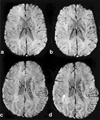

Recently, a new imaging method was proposed by Reichenbach et al (Radiology 1997;204:272-277) to image small cerebral venous vessels specifically. This method, referred to as high-resolution blood oxygen level-dependent venography (HRBV), relies on the susceptibility difference between the veins and the brain parenchyma. The resulting phase difference between the vessels and the brain parenchyma leads to signal losses over and above the usual T2* effect. At 1.5 T, a rather long TE (roughly 40 msec) is required for this cancellation to become significant, leading to enhanced susceptibility artifacts and a long data acquisition time. In this study, we examine the utility of incorporating a clinically available T1 reducing contrast agent, Omniscan (Sanofi Winthrop Pharmaceuticals, NY, NY), with the HRBV imaging approach to reduce susceptibility artifacts and imaging time while maintaining the visibility of cerebral veins. Using a double-dose injection of Omniscan, we were able to reduce TE from 40 to 25 msec. This led to a decrease in TR from 57 to 42 msec, allowing a 26% reduction in data acquisition time while maintaining the visibility of cerebral venous vessels and reducing susceptibility artifacts. J. Magn. Reson. Imaging 1999;10:118-123, 1999.